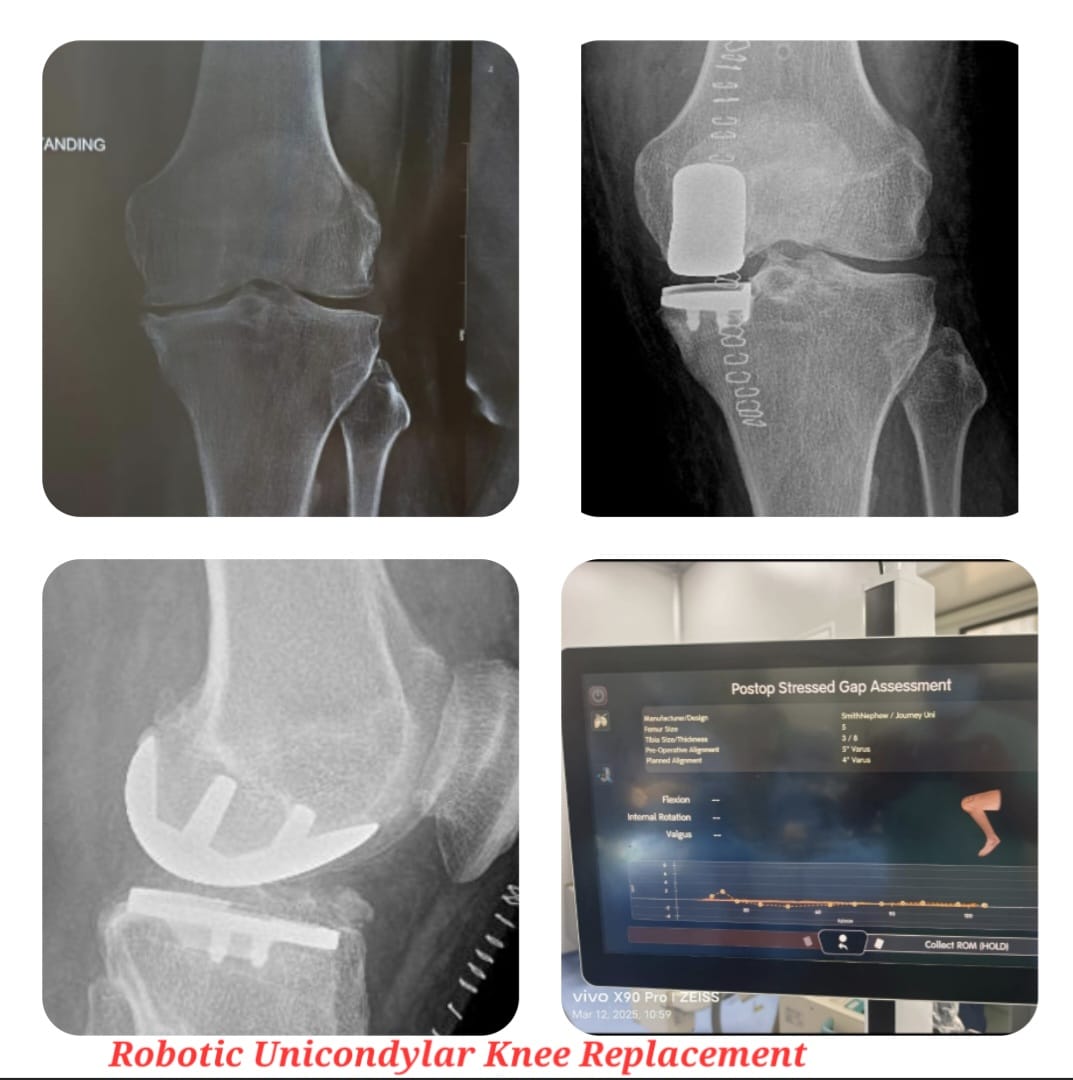

Partial or unicondylar knee replacement is a minimally invasive surgical procedure performed to treat arthritis or cartilage damage limited to one compartment of the knee. Unlike total knee replacement, this procedure preserves healthy bone, cartilage, and ligaments, allowing for more natural knee movement.

This surgery is suitable for carefully selected patients with localized knee degeneration. Advanced surgical planning and precise implant placement ensure optimal joint alignment, stability, and long-term performance while reducing surgical trauma.

Rehabilitation following partial knee replacement focuses on early mobilization, strengthening exercises, and restoring joint confidence. A structured physiotherapy program and regular follow-up ensure optimal healing, implant performance, and long-term functional success.